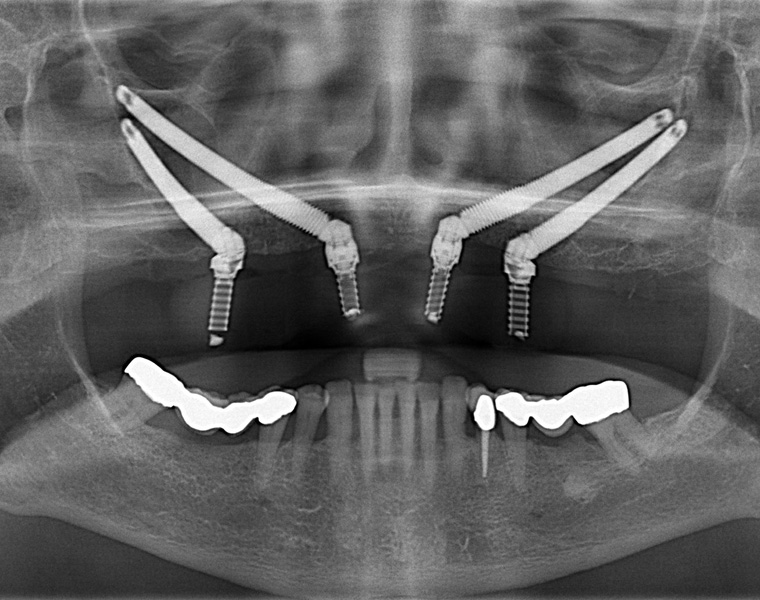

Dental Implants Including Zygomatic Implants

Zygomatic implants are anchored in the cheek bone, which is called the “zygoma” in human anatomy textbooks. The extra-long implant is placed from inside the mouth near the location of the bicuspid teeth. It goes through or right next to the sinus and anchors into the thick and solid zygomatic bone. This bone is much more solid than what is found in the back part of the upper jaw.